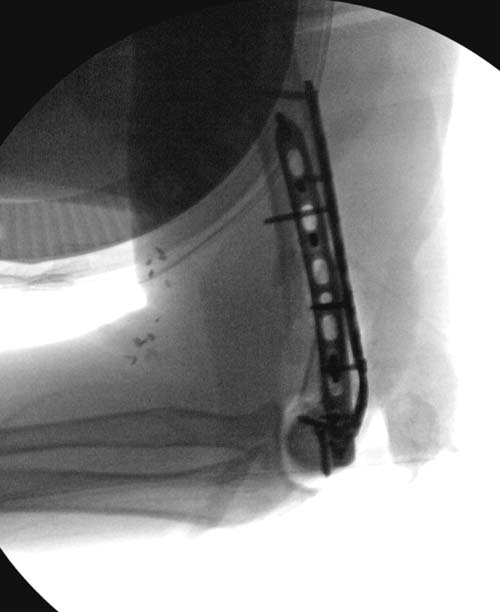

остаться до конца лечения, начал изучать язык... Для облегчения

транспортировки на второй день после поступления правая сторона была

фиксирована ретроградным гвоздем.

Теперь по серьезному. Учитывая качество кости и низкий гемоглобин,

периодический гемодиализ и воодушевленный результатом выступлении

Челнокова, вместо пластины решил попробовать гвоздь. Но жесткие FDА

Гвоздь из ретроградного гвоздя DePuy в 15 мм получился немного тоньше,

чем у Российских коллег.

Операция не обошлась без казуса, при подготовке гвоздя произошла ошибка

в расчете. Пришлось коррегигировать по ходу операции, где длинный

дистальный отдел гвоздя срезали во время операции.

А так вроде первый американский опыт прошел удачно. У больного низкий

гемоглобин, который подправили во время операции переливанием крови.

надеюсь, контрагированные мышцы сохранит длину конечности. Контрольный

снимок показал устойчивую фиксацию.